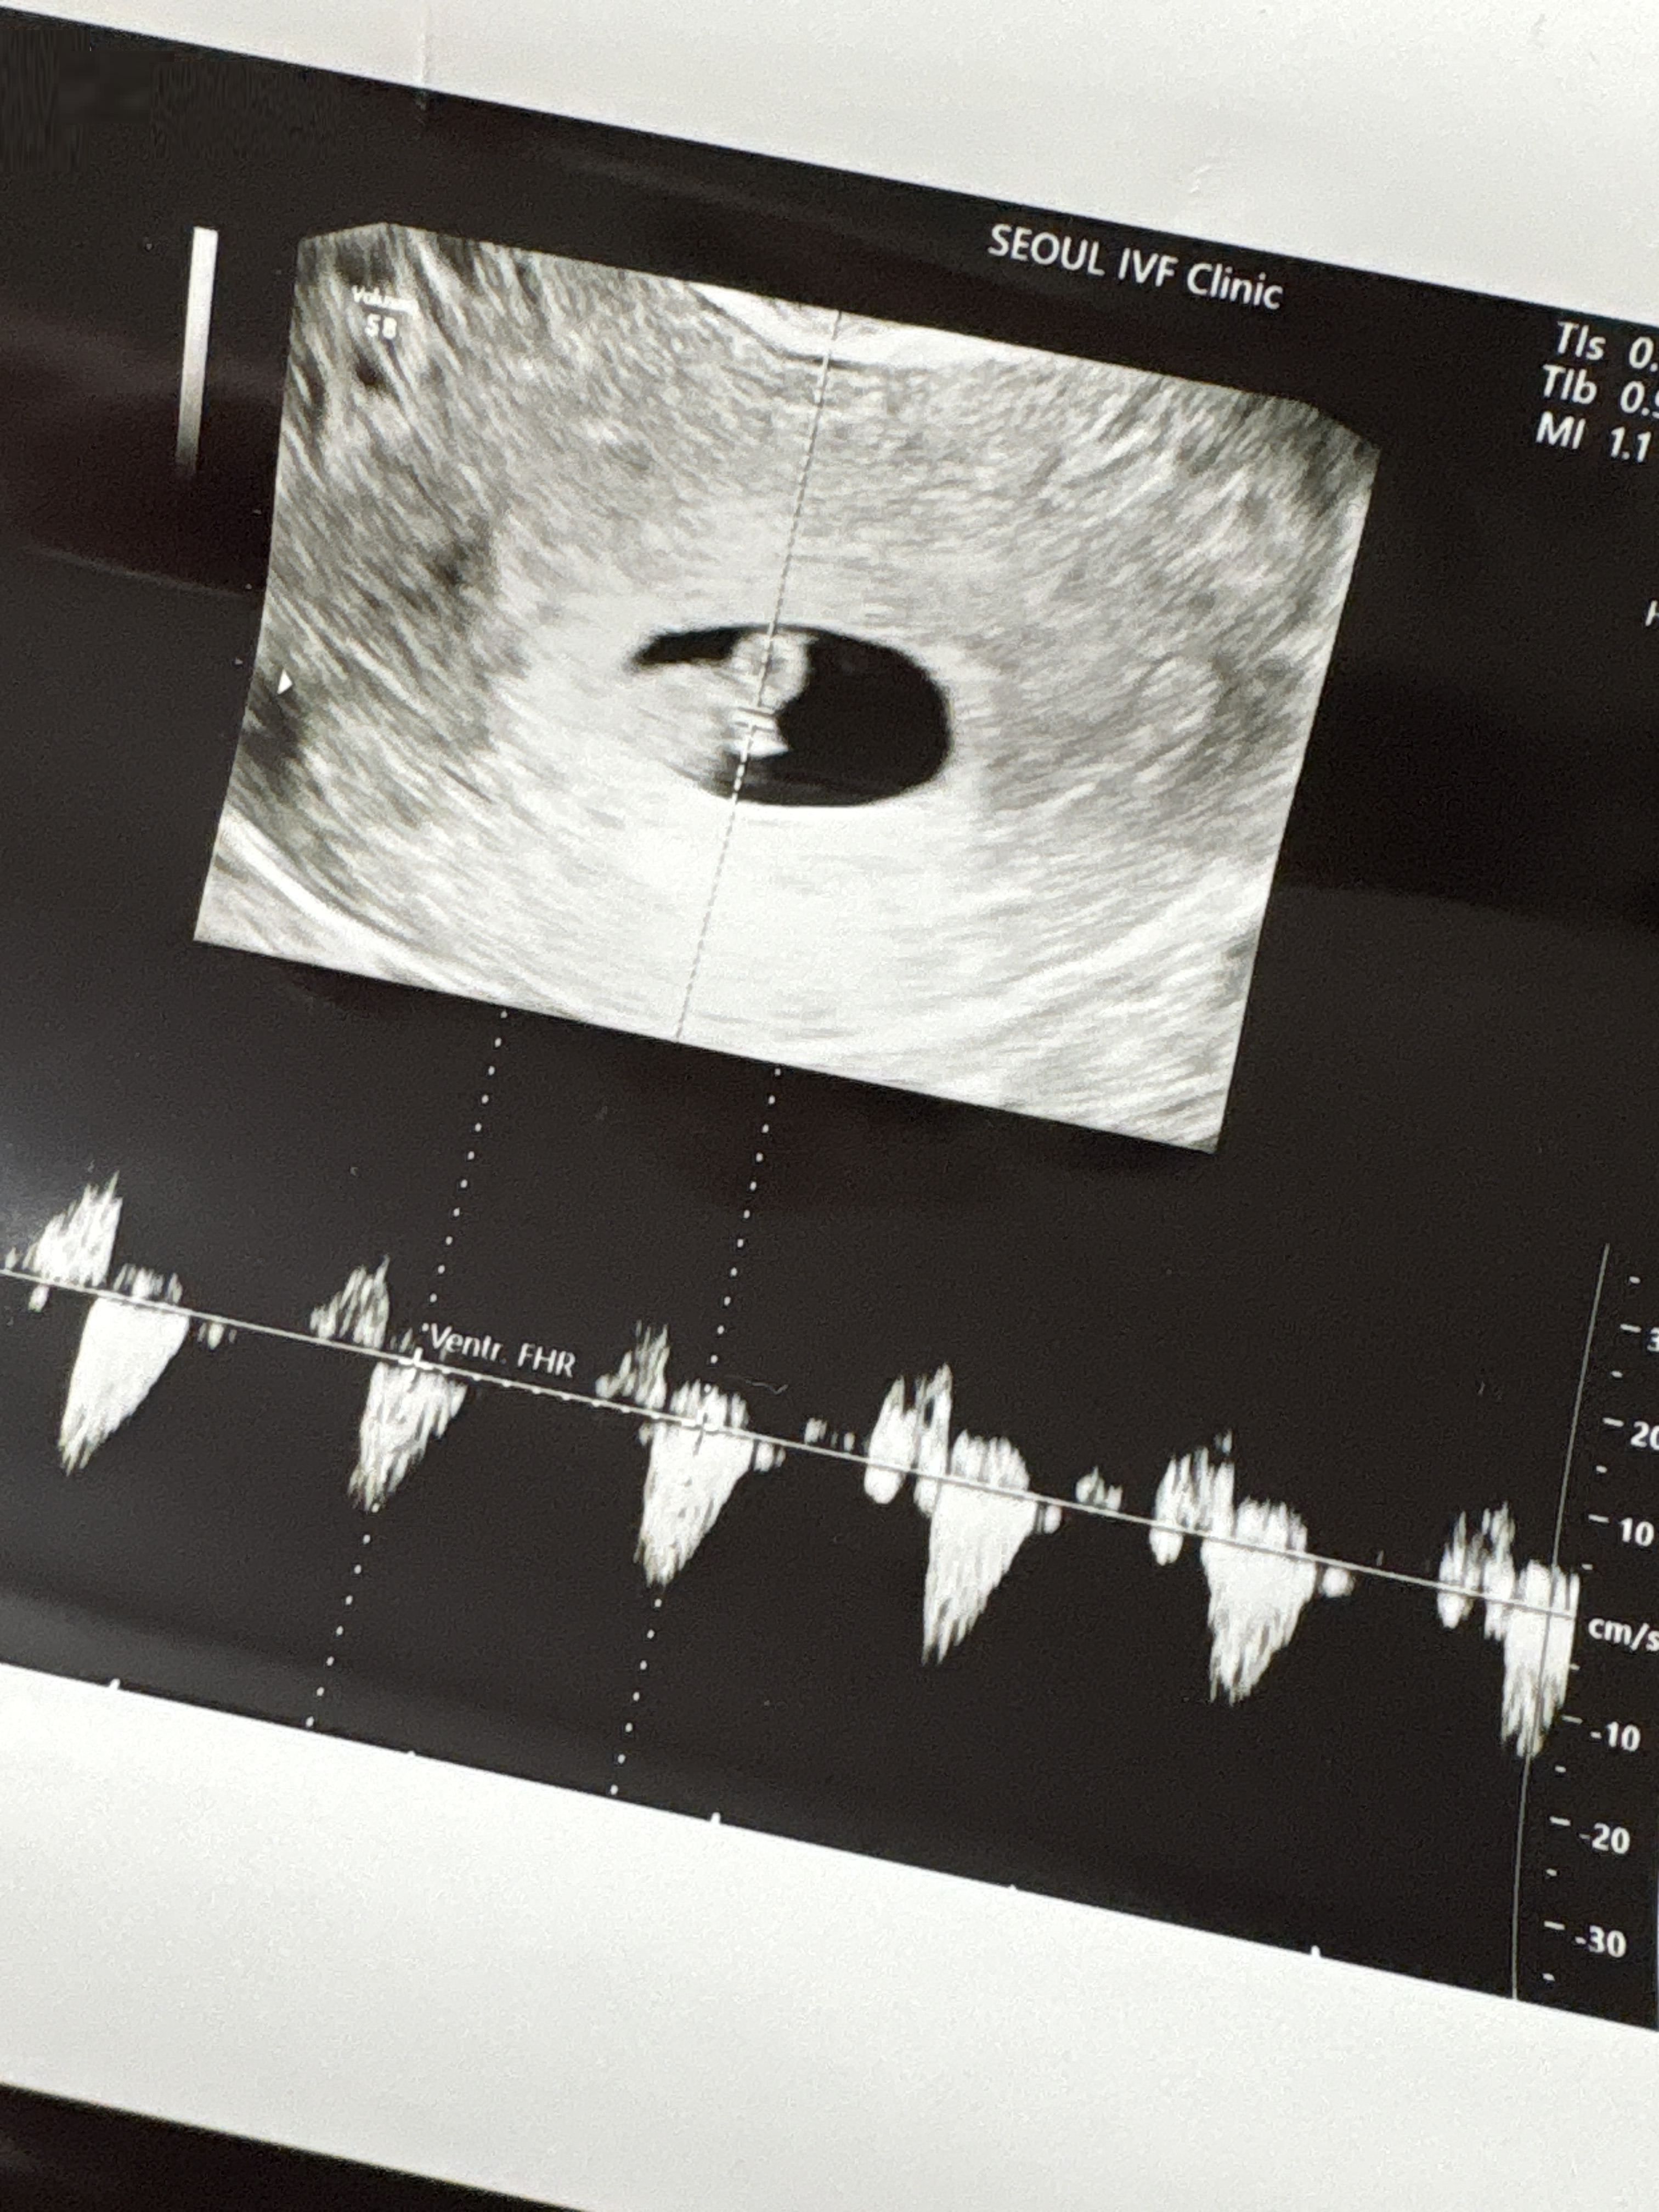

| 가슴 떨리는 임신 이야기를 공유해 주세요. | 아기의 심박수를 듣고 친구들에게 임밍아웃을 했는데, 놀랍게도 친구들 역시 같은 시기에 임신 소식을 전해주었습니다. 그 순간이 더없이 반갑고 특별하게 느껴졌습니다 |

| 치료 도중 느꼈던 가장 기뻤던 순간과 절망적인 것들은 무엇인가요? 잊지 못할 경험이 있나요? | 가장 절망적이었던 순간은 인공수정을 준비하던 중 유산을 겪었을 때였습니다. 반대로 가장 기뻤던 순간은 아기의 심장소리를 듣고, 주변과 기쁨을 나눌 수 있었던 시간이었습니다. |